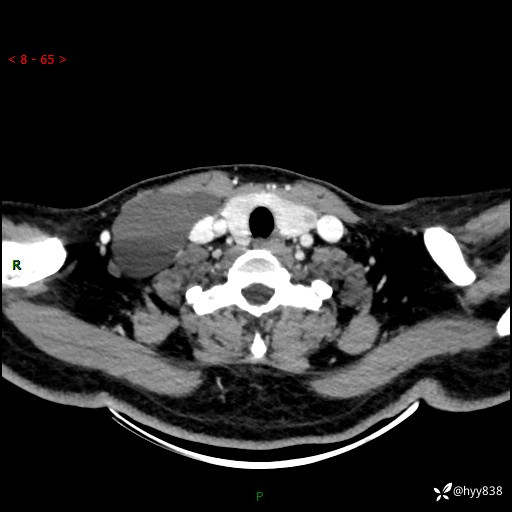

辅助检查:CT

颈部CT平扫

增强动脉期+静脉期